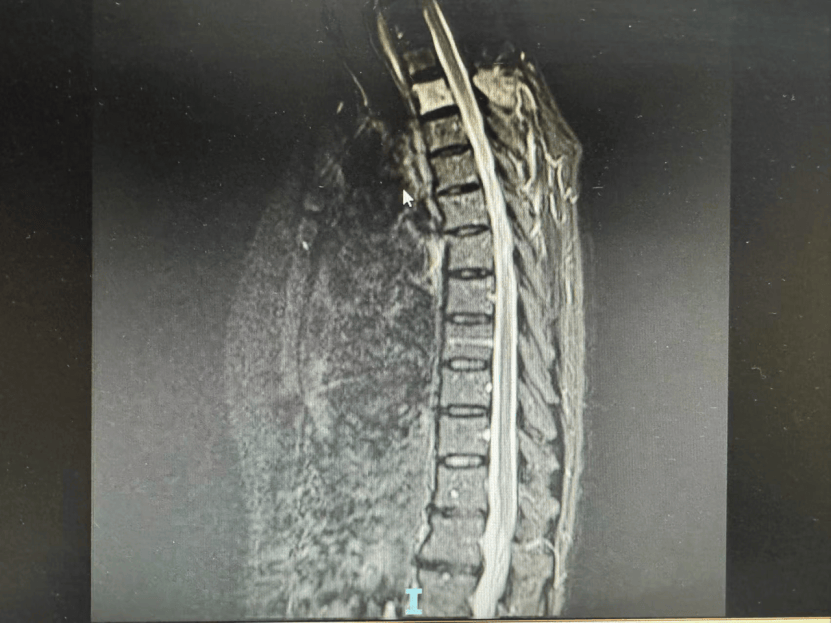

1、癌症骨转移不能自愈发生机制肿瘤细胞通过血液或淋巴系统转移至骨骼后,会分泌破骨细胞激活因子等物质,激活破骨细胞并抑制成骨细胞功能,导致骨吸收增加骨形成减少,破坏骨代谢平衡例如,乳腺癌细胞转移至骨组织时,会释放转化生长因子β等物质,促进破骨细胞活化和增殖,进而引发骨破坏影响因素;总结恶性骨肿瘤的预后与病理类型分期治疗规范性密切相关早期原发性肿瘤有望治愈,转移性肿瘤可长期带瘤生存,晚期病例则以改善生活质量为核心定期筛查早期诊断和个体化综合治疗是提高预后的关键;癌症骨转移不能自愈癌症骨转移是原发肿瘤通过血液或淋巴系统扩散至骨骼后形成的继发性病变,其本质是肿瘤细胞在骨组织中的异常增殖这一过程会破坏骨结构,引发剧烈骨痛病理性骨折高钙血症等严重并发症,甚至危及生命由于肿瘤细胞具有无限增殖的特性,且骨转移灶往往伴随局部微环境改变如血管生成;积极治疗不仅能控制病情进展,还能改善疼痛活动能力等生活质量指标结论骨肉瘤骨转移虽提示病情加重,但通过化疗局部治疗及新型疗法的综合应用,患者仍可获得较长的生存期和较好的生活质量早期诊断规范治疗和定期随访是关键,患者应保持信心并配合医疗团队制定个体化方案;3 靶向治疗针对肿瘤细胞特定分子靶点如EGFRALK设计药物,具有高选择性和低毒性,适用于存在驱动基因突变的患者,可显著延长生存期4 手术治疗适用于单发骨转移瘤或承重骨如脊柱股骨威胁骨折的情况,通过切除病灶或加固骨骼结构,预防严重并发症5 止痛治疗遵循三阶梯止痛原则,从非。

2、单一转移且原发灶可控时,可采取根治性切除若骨转移为单一病灶,且原发肿瘤如肺癌已通过手术或其他治疗得到良好控制,此时可将骨转移瘤视为原发性骨肿瘤处理例如,肺癌患者肺部病灶稳定后,若仅发现一处骨转移,可通过手术彻底切除转移灶,达到根治目的这种策略的核心是将转移灶视为局部疾病,通过;前列腺癌骨转移虽难以完全治愈,但通过综合治疗可有效控制病情缓解症状提高生活质量并延长生存期具体分析如下综合治疗是核心策略前列腺癌骨转移的治疗需结合多种方法,包括雄激素剥夺治疗ADT放疗化疗内分泌治疗靶向治疗和骨保护治疗等ADT通过药物或手术去除雄激素,抑制肿瘤生长放疗针对;手术治疗主要针对单发骨转移瘤通过彻底切除肿瘤组织,可有效减轻疼痛并恢复骨骼功能,但需严格评估患者身体状况及转移范围,确保手术安全性综合治疗强调多手段协同例如,化疗联合放疗可增强局部控制效果靶向治疗联合免疫治疗能提升抗肿瘤活性具体方案需结合患者年龄性别身体状况肿瘤类型及转移部位等;肺癌骨转移能否治愈需分情况讨论,总体治愈概率较低,但部分患者存在治愈可能少数患者可能达到临床治愈这类患者的肺癌类型通常对靶向药物或化疗药物高度敏感例如,携带特定基因突变如EGFR突变ALK融合的非小细胞肺癌患者,通过靶向治疗可显著抑制肿瘤生长若同时配合抑制破骨细胞活性的药物如双膦酸;癌症骨转移不能自愈癌症骨转移是恶性肿瘤通过血液或淋巴系统扩散至骨骼后形成的继发性病变,其本质是肿瘤细胞在骨组织中的增殖与破坏,这一过程具有不可逆性,无法通过机体自身修复机制实现自愈癌症骨转移的治疗需以缓解症状控制肿瘤进展提高生活质量和延长生存期为核心目标具体方法包括放疗通过;骨转移之后可能会造成局部骨的强度下降,破骨细胞活跃,癌细胞将局部的骨组织吞噬,所以在低暴力的时候就容易发生病理性骨折,造成顽固性的疼痛,特别是晚期肿瘤患者最常见,而且也是最难以解决的问题,严重影响患者的生活质量和预后转移性骨肿瘤的放射性药物治疗能明显的缓解疼痛,是有效的止痛治疗方法对。

3、肺癌骨转移目前尚无法完全治愈,但通过综合治疗和科学管理可显著延长生存期并改善生活质量患者存活五年属于相对较长的生存情况,提示病情得到一定控制,但需结合以下因素综合判断预后一预后意义与肿瘤生物学特性存活五年表明肿瘤增殖活性较低,转移灶发展缓慢,可能存在抑癌基因表达稳定等有利分子机制但。

4、癌症发生骨转移并不意味着无法治疗,通过综合治疗可以延长生命并提高生活质量骨转移是恶性肿瘤晚期的一种常见并发症,代表着肿瘤细胞已经扩散至骨骼组织虽然骨转移意味着肿瘤的清除变得更加艰难,但并不意味着病情无法控制或治疗无效通过合理的综合治疗,可以降低骨恶性事件的发生,延长患者的生存期,并。

5、乳腺癌骨转移能否治好需分情况讨论,无法一概而论部分患者可能达到临床治愈若乳腺癌骨转移的病灶数量较少以成骨性破坏为主即骨骼修复反应活跃,且全身治疗效果显著,如使用二膦酸盐类药物有效控制骨代谢异常抑制破骨细胞活性,同时配合系统治疗如化疗靶向治疗或内分泌治疗控制原发肿瘤;目前并没有能够治愈骨转移的药物,但可通过药物治疗缓解症状控制肿瘤进展骨转移是癌症晚期常见的并发症,治疗需根据患者具体情况制定个性化方案,常用药物及方法包括以下几类双膦酸盐类药物通过抑制破骨细胞活性,减少骨吸收,缓解骨痛并预防骨折等并发症常用药物包括唑来膦酸伊班膦酸,需定期静脉。

6、3 骨转移癌骨转移癌的生存率因原发肿瘤类型转移范围及患者基础状态而异例如乳腺癌前列腺癌骨转移患者通过系统治疗如内分泌治疗放疗核素治疗可存活数年,而肺癌骨转移患者生存期可能较短现代多学科治疗如骨水泥成形术靶向药物已显著延长生存期并改善症状,但治愈仍属罕见总结骨;肝癌骨转移不能一概而论能否治好,但合理治疗可改善症状延长生存提高生活质量全身治疗系统抗肿瘤治疗是关键手段之一对于存在特定驱动基因变异的肝癌骨转移患者,靶向药物可通过抑制肿瘤细胞生长和扩散,对骨转移病灶产生控制效果免疫治疗药物则通过激活人体免疫系统攻击肿瘤细胞,部分研究显示其能改。